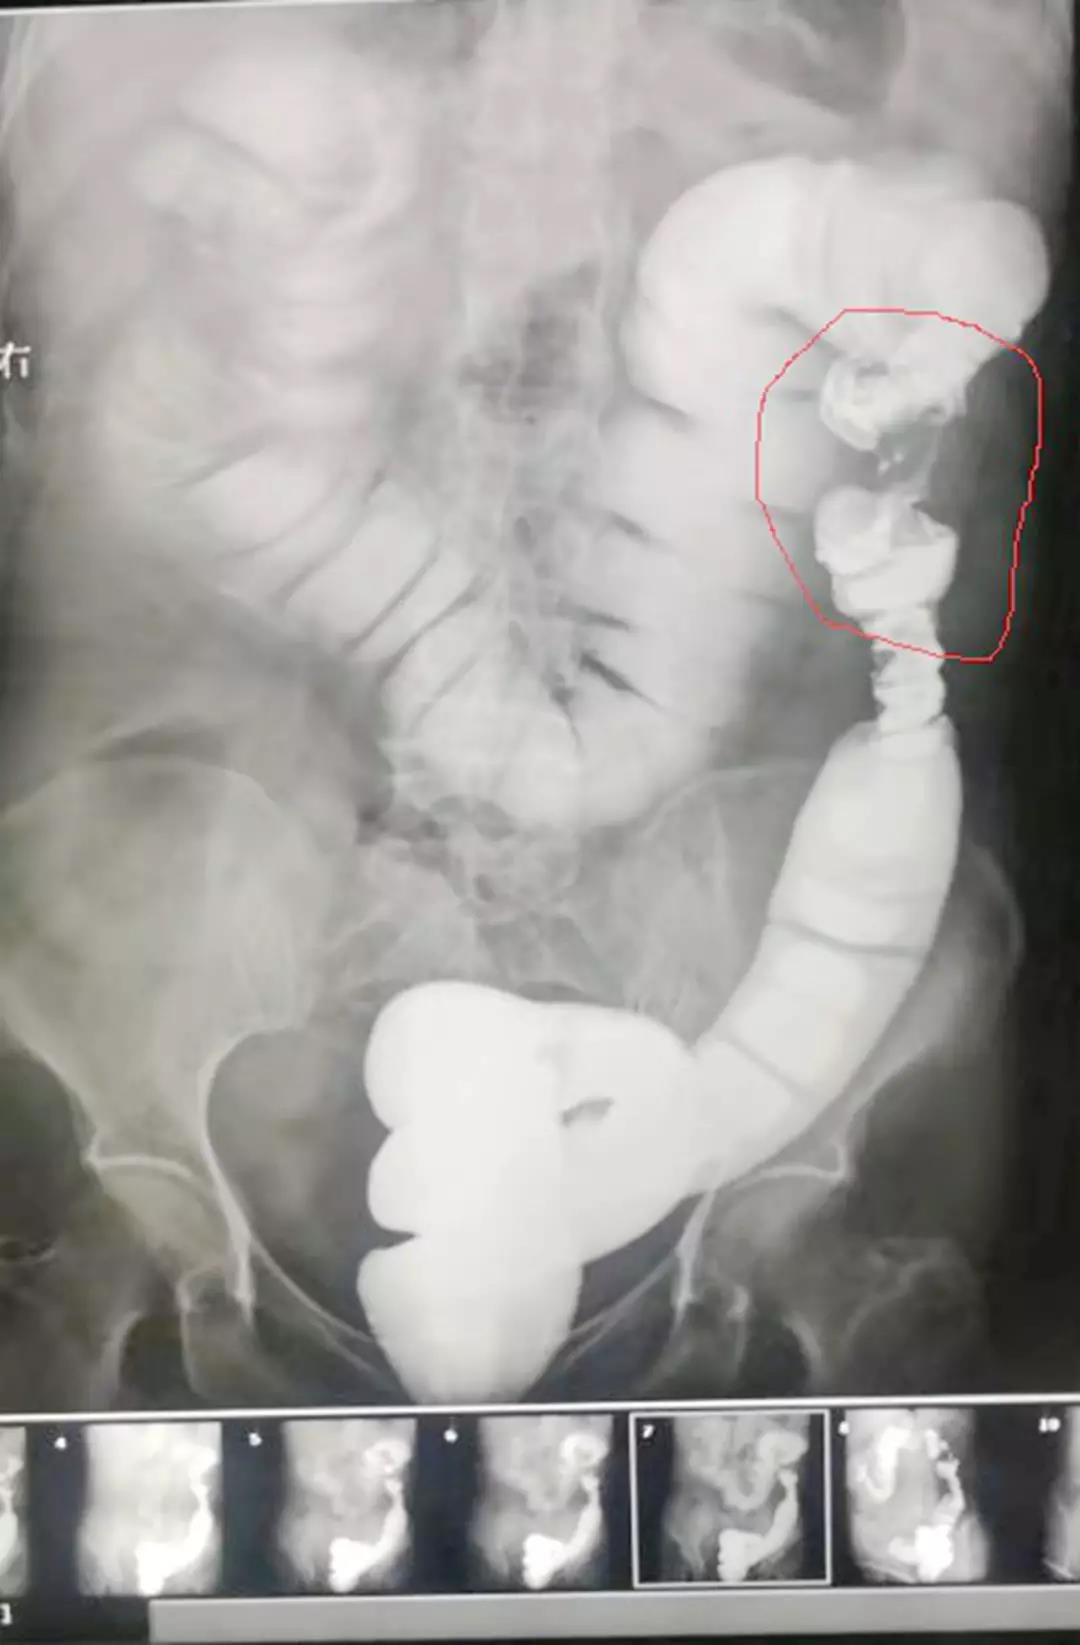

(钡灌肠造影检查所示:降结肠“苹果核征”:降结肠脾区局部狭窄,两端呈肩状,中央管腔狭窄,并有粘膜破坏,中断,边缘不规整,形似被吃剩的苹果核。)